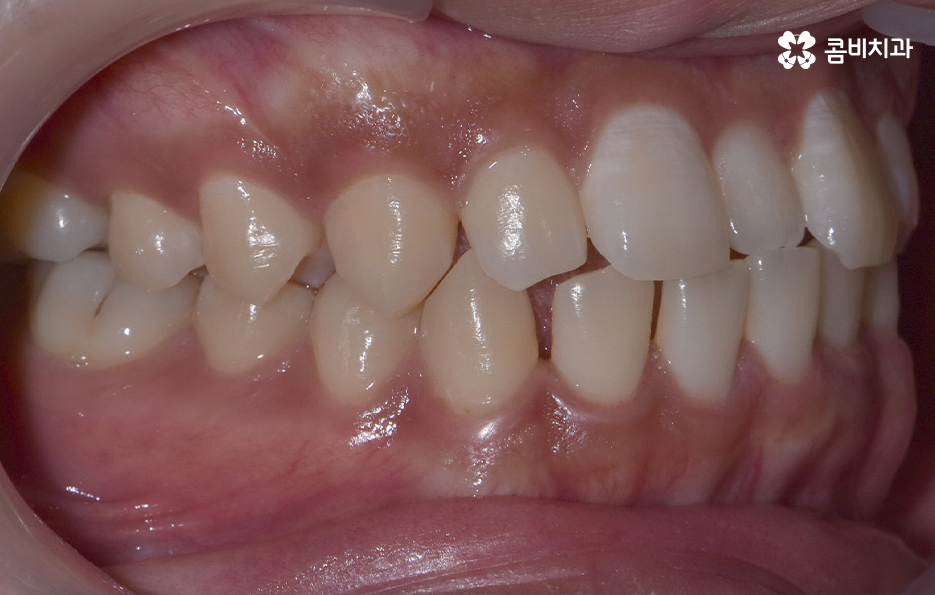

과잉치 중에서는 어떤 치아가 과잉치인지 구분이 어려울 정도로 일반적인 정상 치아의 크기와 비슷한 크기와 형태를 띄는 경우도 있는 반면에 위 사진의 케이스는 첫번째 앞니와 앞니 사이에 유독 작은 왜소치가 있는 형태이기 때문에 치아의 기능적인 문제 보다는 심미적인 개선을 필요했던 케이스로 볼 수 있어요

그나마 다행인 점은 앞니만교정을 하더라도 치아의 교합이나 골격적인 부분, 얼굴형 등에 있어서 큰 지장은 없던 경우였는데요. 물론 아랫니가 다소 벌어져 있기 때문에 전체교정을 하면 더 좋은 결과를 얻을 수 있었겠지만 환자분의 니즈에 있어서 앞니만교정을 빠르게 원했던 사례이기 때문에 앞니 부분의 과잉치 발치 후 앞니만교정을 부분적으로 진행했어요

과잉치로 인해서 치아 배열이 전체적으로 불규칙해지는 경우도 있고 돌출입의 형태로 나타는 경우도 있지만 다행이도 입술라인이나 얼굴형에 있어서 돌출은 크지 않은 상태였다는 점도 앞니만교정을 해도 어느정도 좋은 결과를 낼 수 있던 케이스로 볼 수 있어요

과잉치로 인해 말그대로 치아의 정상 범위 이상으로 치아가 배열되기 때문에 다른 치아의 배열에도 악영향을 주는 경우가 많지만 위 환자분의 케이스의 경우에는 치열 자체는 전체적으로 가지런한 편이라는 점과 특히 턱뼈가 넓은 편이라는 점에서 전체교정을 하지 않았어도 환자분이 원하는 치료의 목표는 달성할 수 있었어요